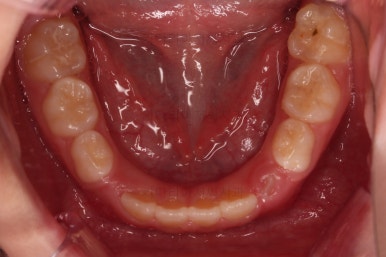

장치 사용 4달째 모습입니다.

벌써 개방교합이 개선되고 있고, 반대교합도 많이 좋아져서 거의 위아래 앞니가 비슷한 위치까지 왔네요.

치료 9개월째입니다.

앞니끼리 거의 겹칠 정도로 개방교합은 거의 개선되어가고요. 윗니도 아랫니 보다 살짝 앞으로 나오기 시작했네요.